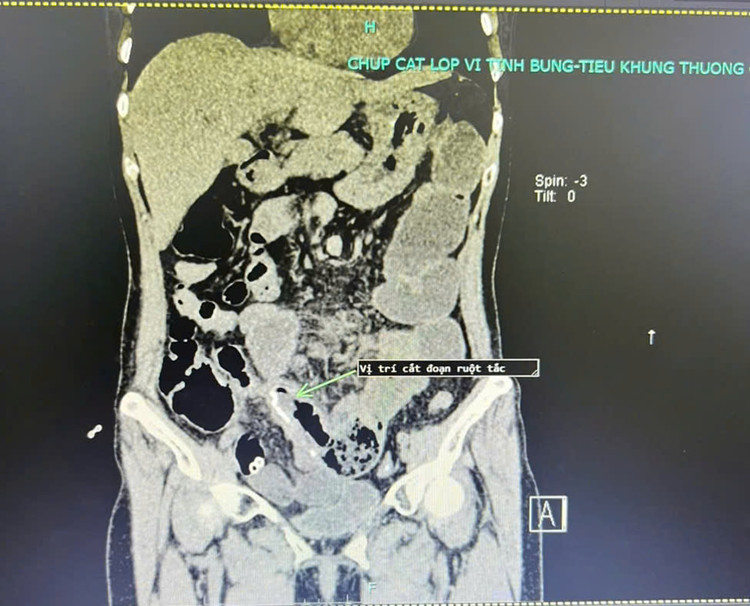

| Hình ảnh chụp cắt lớp vi tính sau khi phẫu thuật của người bệnh, tình trạng tắc ruột đã cải thiện rõ rệt. Ảnh BVCC |

Trong mổ các BS nhận thấy các quai ruột non giãn to, dính gập góc gây tắc hoàn toàn đoạn hồi tràng gần góc hồi manh tràng. Các Bs đã tiến hành gỡ dính, cắt đoạn ruột tắc lập lại lưu thông ruột. Hiện tại, người bệnh đã ổn định và được ra viện.